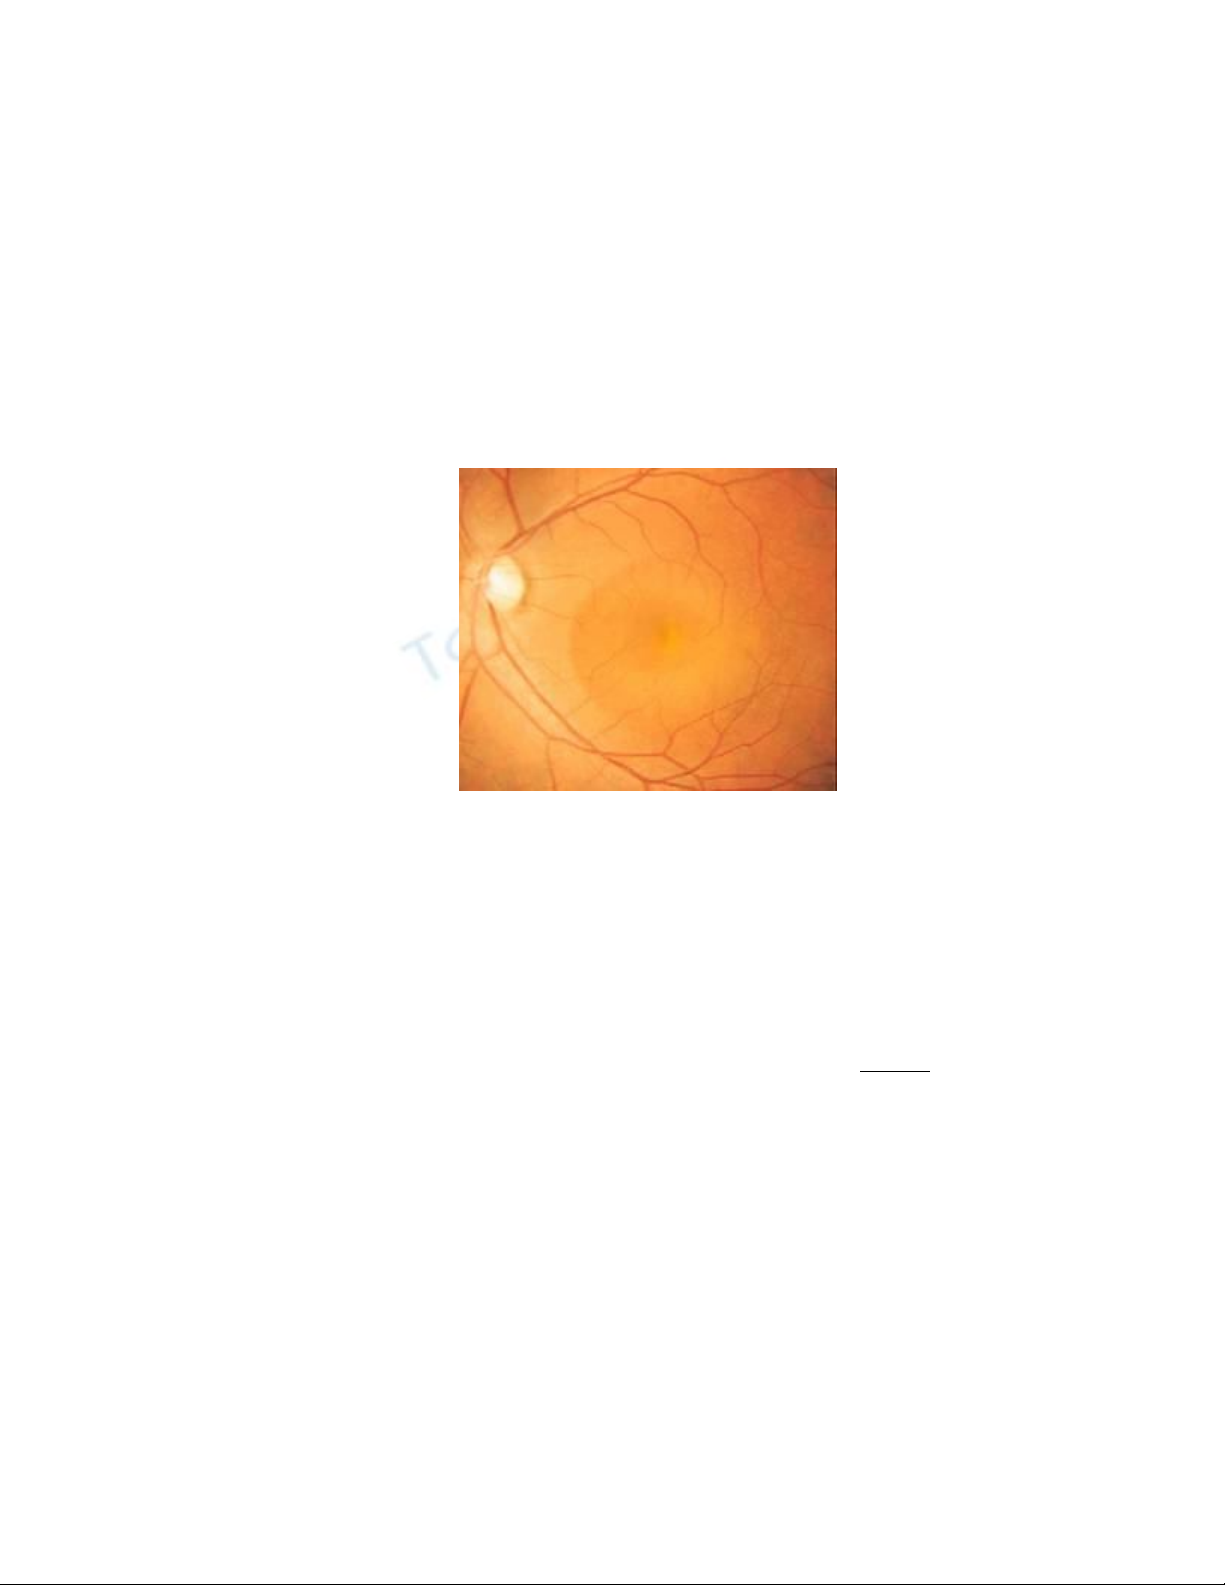

Võng mạc

Võng mạc (retina) là lớp tế bào nhậy cảm với ánh sáng, lót phía trong mắt.

Đây là cấu trúc căn bản của cặp mắt, có công dụng như tấm phim của máy

ảnh để thu nhận và ghi lại cả muôn vàn hình ảnh, tĩnh cũng như động, suốt ngày

này qua tháng khác mà không cần thay phim như trong máy ảnh…

Trên võng mạc có những tế bào hình nón, hình que chuyển ánh sáng từ bên

ngoài vào thành những tín hiệu điện năng, được dây thần kinh thị giác đưa lên não

bộ. Tế bào não phân tích, tổng hợp các tín hiệu và tạo ra hình ảnh của sự vật.